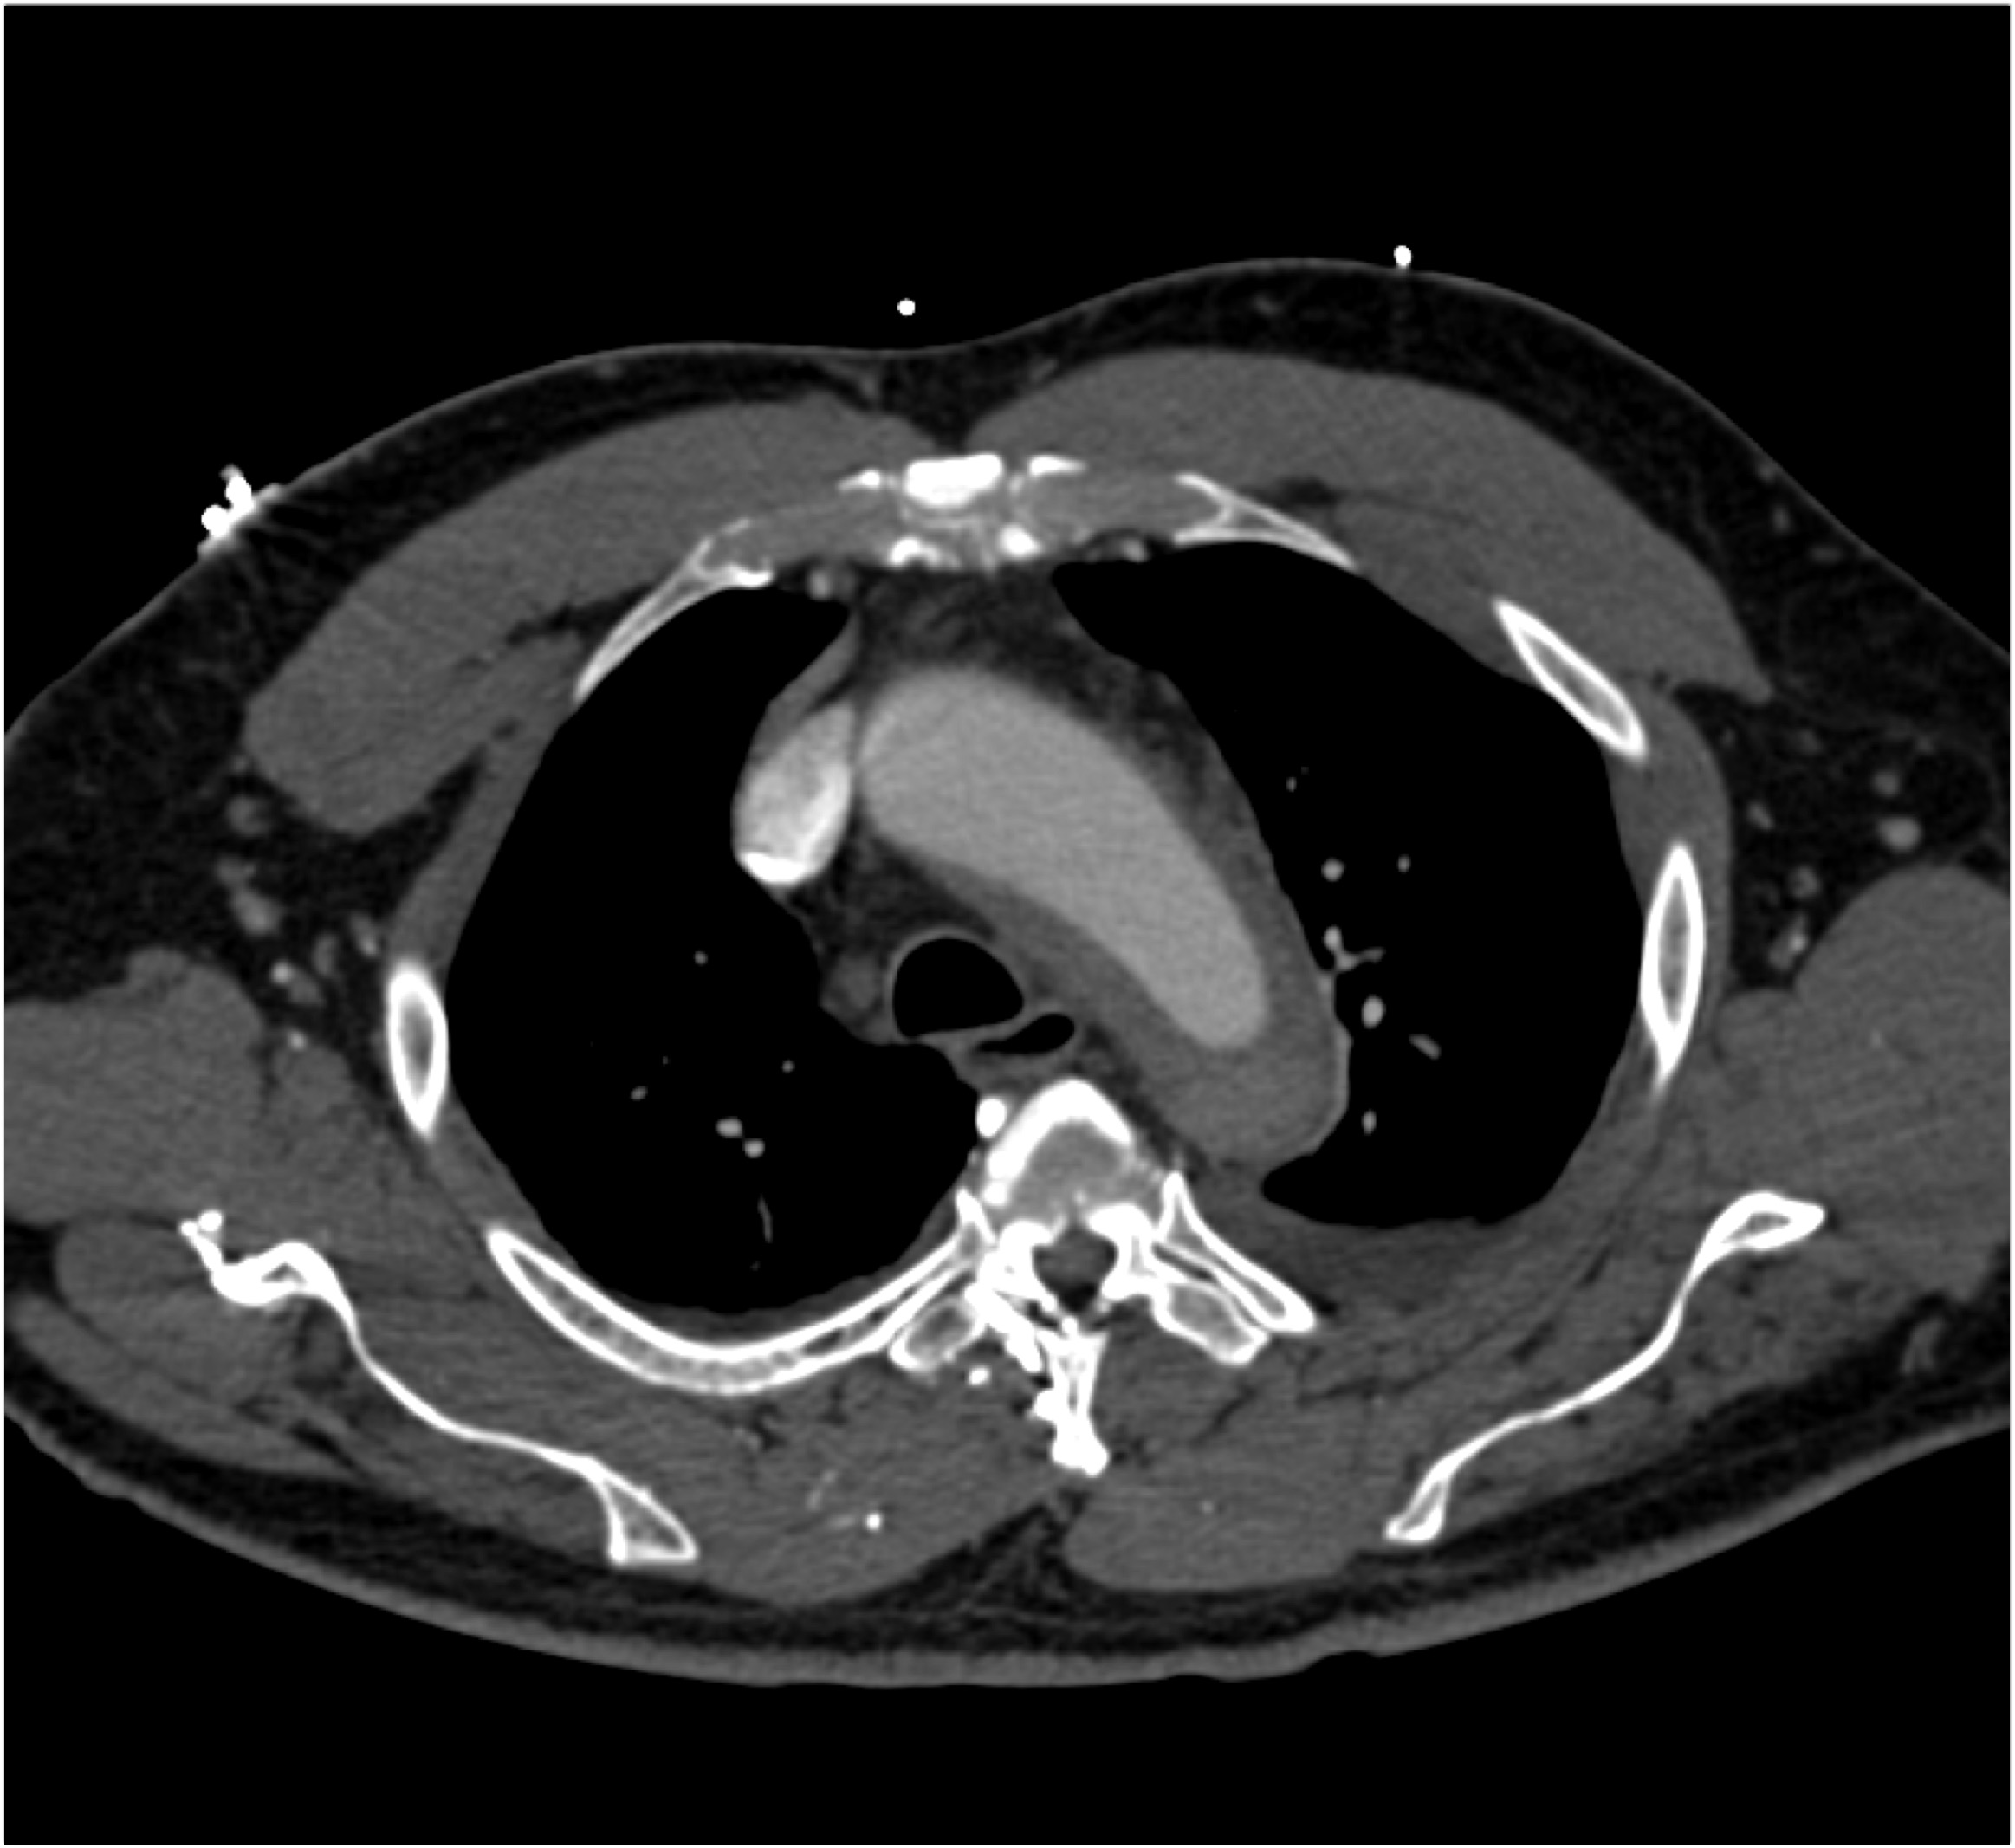

7) The most likely diagnosis in this case is?

Ehlers Danlos disease

Kawasaki disease

Takayasu’s aortitis

Ig4 vasculitis